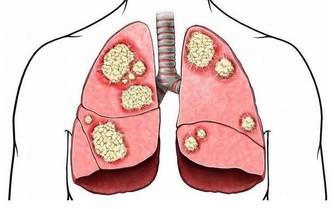

如果將好血管和“生了病”的血管放在你面前,你會發現,

好的血管看上去特別舒服,動脈血管富有活力,管壁十分光滑,看不到什麼雜質,這种血管輸送血液的能力也最強。

但“生了病”的血管,其管道內壁就被各種“垃圾”佔據,形成如同黃色小米粥樣的斑塊,

久而久之血液流動受阻,最終因缺血引發多種疾病。